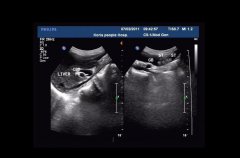

•   患膽結(jié)石需做超聲檢查 日期:2016-01-06 08:12:00 點擊:2334 好評:37

膽結(jié)石病又稱膽系結(jié)石病或膽石癥,是膽道系統(tǒng)的常見病,是膽囊結(jié)石、膽管結(jié)石(又分肝內(nèi)、肝外)的總稱。膽結(jié)石應(yīng)以預(yù)防為主,發(fā)病后應(yīng)即時治療,一般有非手術(shù)及手術(shù)治療兩類治療手段...